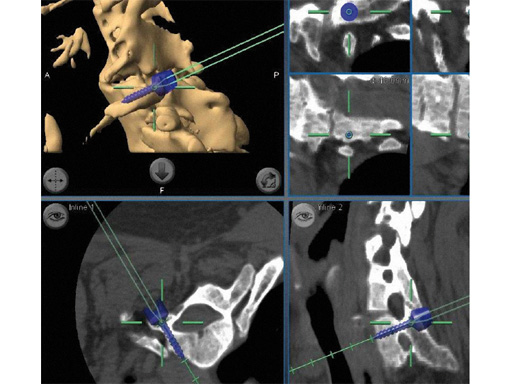

Intraoperative CT scans can be obtained using image-intensification- based isocentric C-arms, portable cone beam CT (O-arm, Medtronic) or true intraoperative CT scanners (iCT). Isocentric C-arms and portable scanners offer the advantage that they can also be used as regular C-arms, however their imaging quality may be inferior to stationary CT scans (Fig 3).

Fig 3ac a Intraoperative CT scans from an image-intensification-based isocentric C-arm. The software allows simulation of various diameter and length screws. bc Comparison of intraoperative simulation and postoperative CT scan shows the high accuracy of CAS.